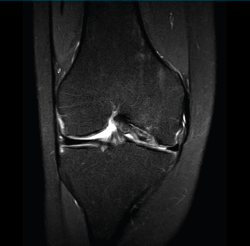

1.2.2. Ligamento cruzado anterior (LCA) (Figuras 40, 41, 42, 43 y 44)

Figura 40. Corte de secuencia sagital T2 Fat-Sat de resonancia magnética de rodilla: ligamento cruzado anterior normal.

Figura 41. Cortes de secuencia sagital T2 Fat-Sat de resonancia magnética de rodilla: rotura central del ligamento cruzado anterior.

Figura 42. Cortes de secuencia sagital T2 Fat-Sat: rotura proximal del ligamento cruzado anterior.